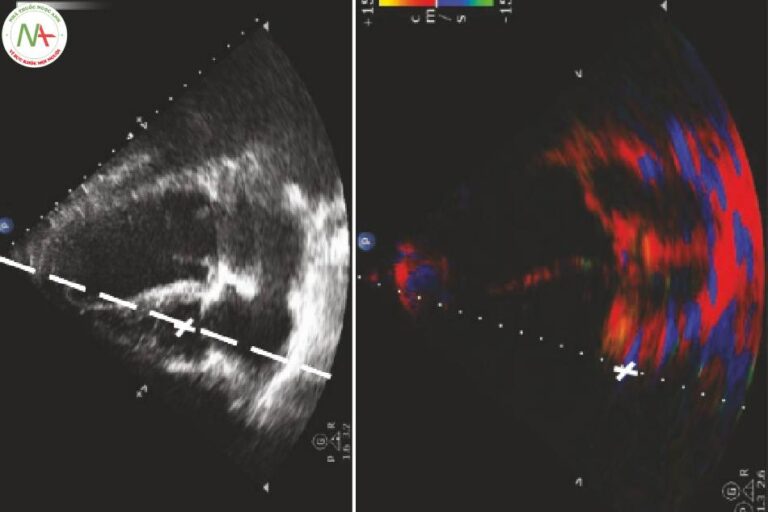

Các phép đo và phân tích trong siêu âm khi hồi sức